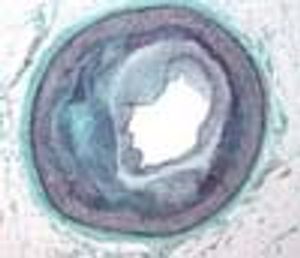

Inflammation plays a major role in coronary artery disease (CAD), whereby inflammatory changes develop in the blood vessel walls.1 This observation has spurred interest in exploring the connection between CAD and markers of inflammation, including C-reactive protein (CRP), fibrinogen, serum amyloid A, and many other novel markers.